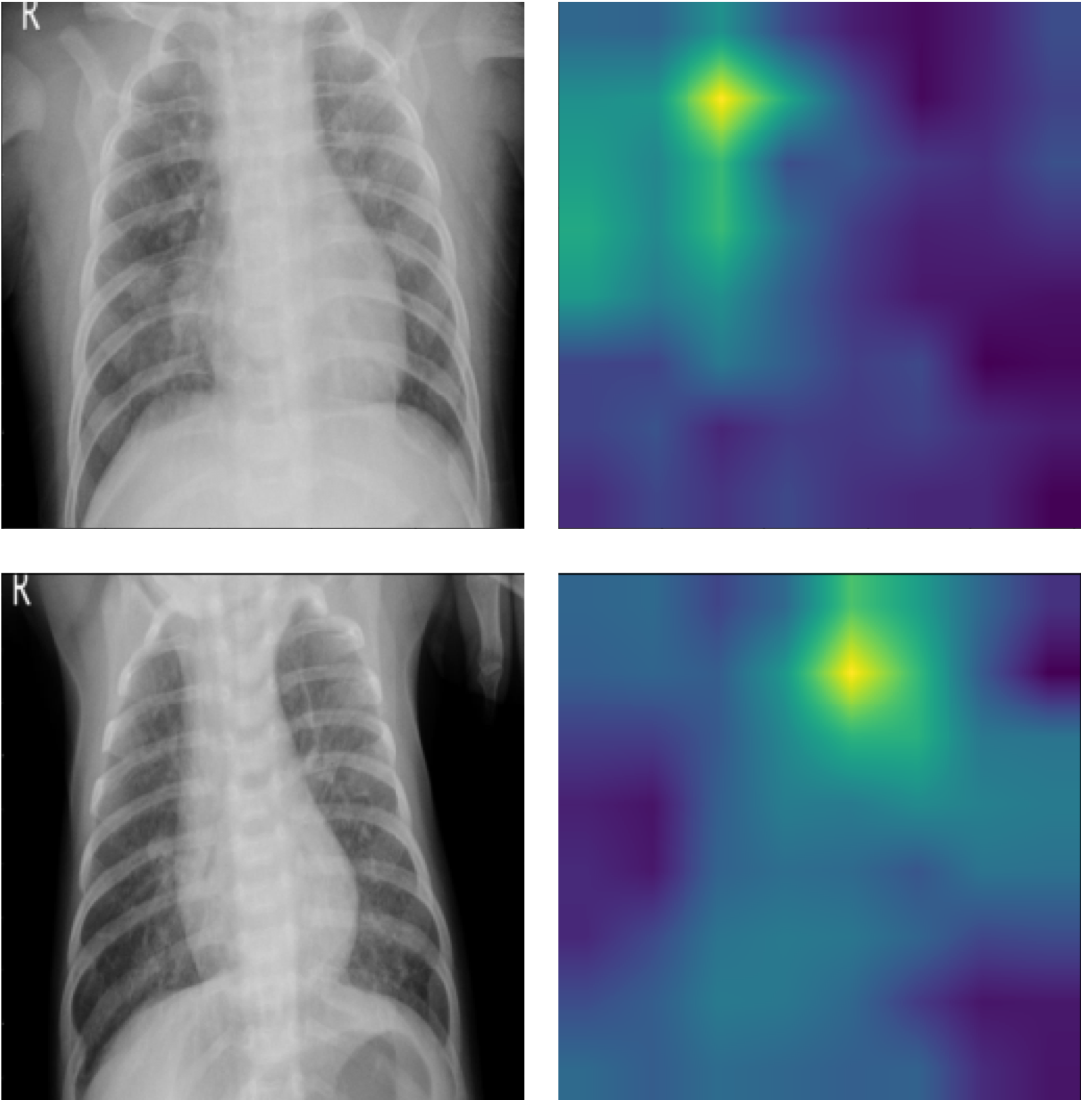

Figure 6 shows two class activation mapping (CAM) [68] visualizations for the pediatric pneumonia diagnosis that performed by Ours. The pixel values in the CAMs are associated with the contribution to the classification decision. A higher value (brighter color) indicates a higher contribution to the class decision. Both cases in the figure are ground-truth positive cases. The CAMs reveal that the model correctly focuses on the corresponding areas that show some concerns about pneumonia.

Refer to caption

Figure 6: Two CAM visualizations for pediatric chest X-ray pneumonia classification on the Mendeley-V2 dataset with chest X-ray on the left and CAM on the right. The CAMs reveal that the model correctly focuses on the corresponding areas show some concerns about pneumonia.